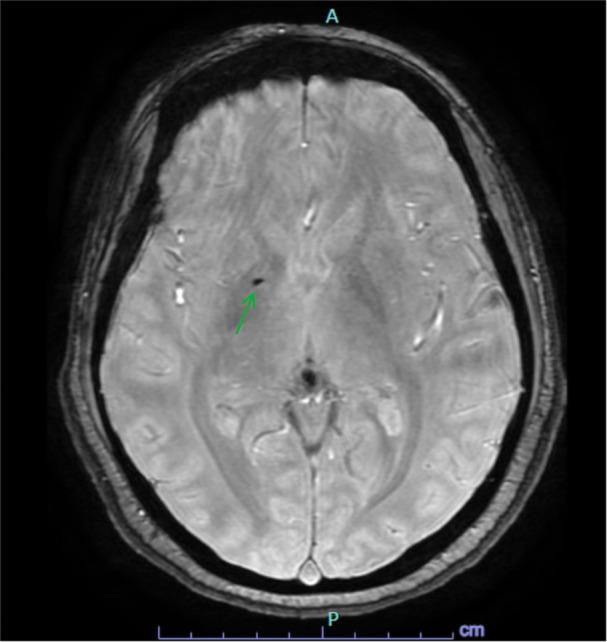

A rare type of hemolytic anemia caused by hemoglobin (Hb) Manukau is reported in a 30-year-old female presenting with 3 weeks of severe depression, paranoia, auditory hallucinations, and suicidal ideation. The client was admitted to a psychiatric unit and received treatment with sertraline and olanzapine. Post-discharge follow up is with a community mental health team. The psychiatric history includes recurrent episodes of major depression with psychotic features, with the first occurring after a stillbirth at age 18 years. The treatment history includes electroconvulsive therapy, sertraline, and olanzapine. The medical complications of the Hb Manukau are chronic hemolytic anemia, liver disease, and hemochromatosis, requiring frequent blood transfusions and iron chelation therapy.

This rare hemoglobinopathy may contribute to the pathogenesis of recurrent depression with psychotic features, potentially through iron deposition in the brain or by other mechanisms yet to be defined.